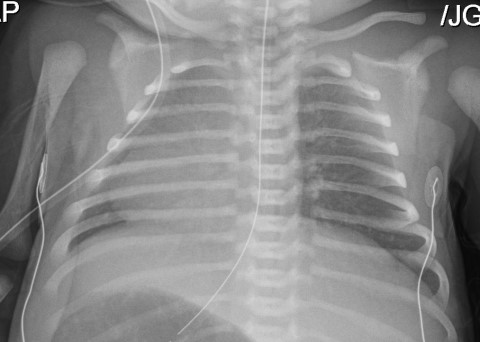

- Neonatal respiratory distress

- Unexplained neonatal respiratory distress (at term birth) with lobar collapse and/or need for respiratory support with CPAP and/or oxygen for >24 hr